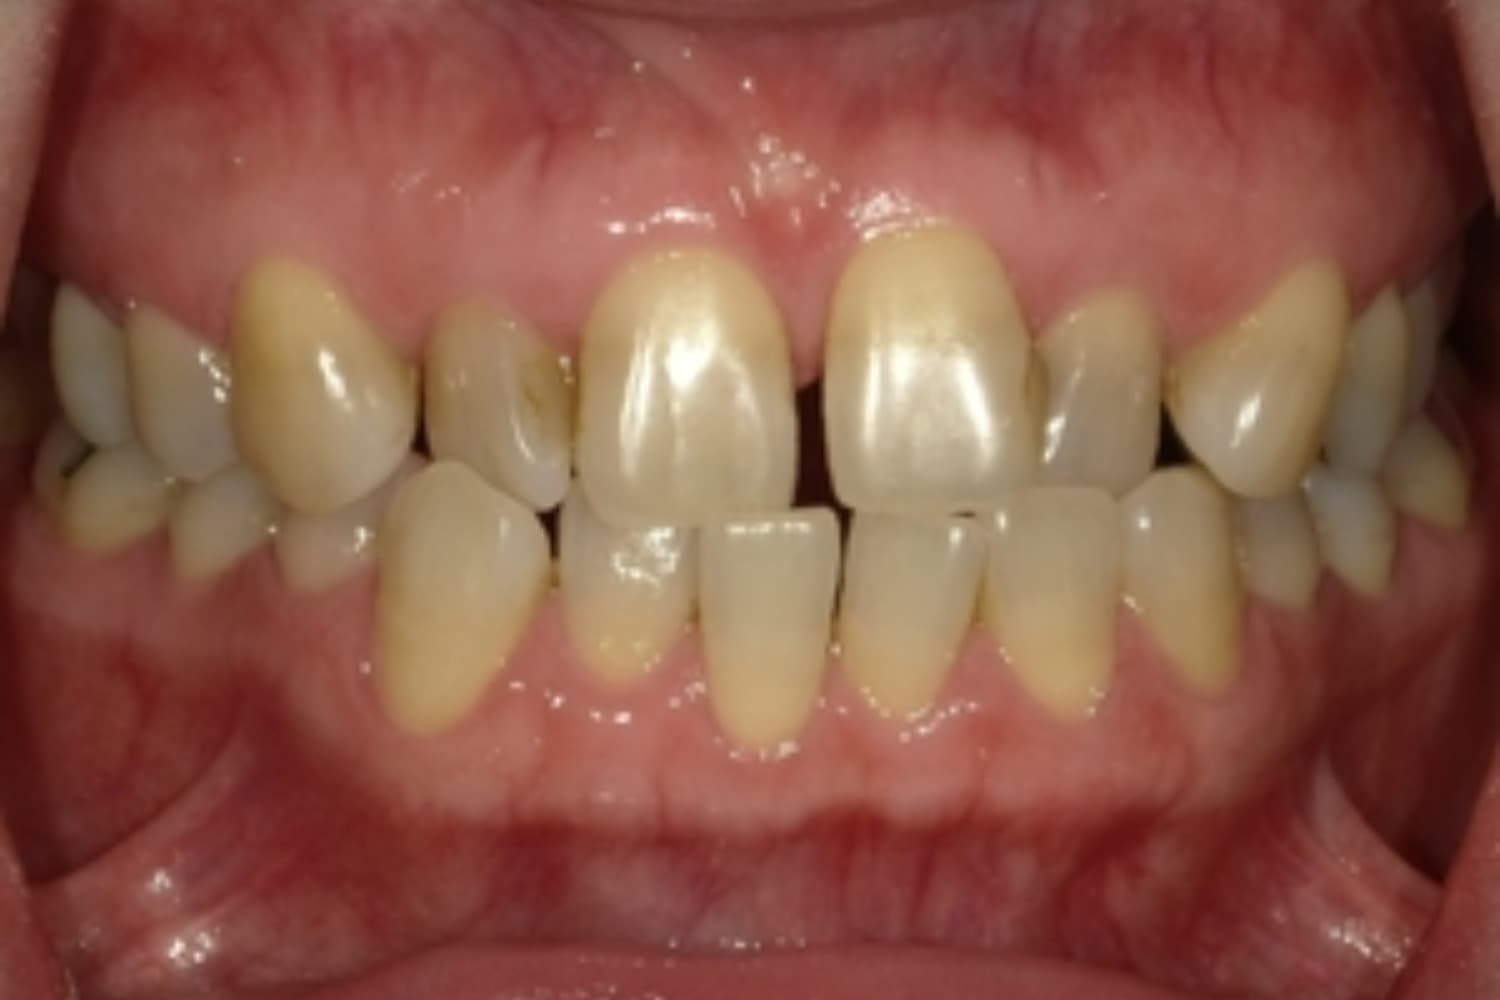

すきっぱ(空隙歯列)

Before

After

気になる前歯の隙間と前歯のガタガタをマウスピース矯正(インビザライン)にて治療

治療期間

1年5カ月

費用

66万円(税込)